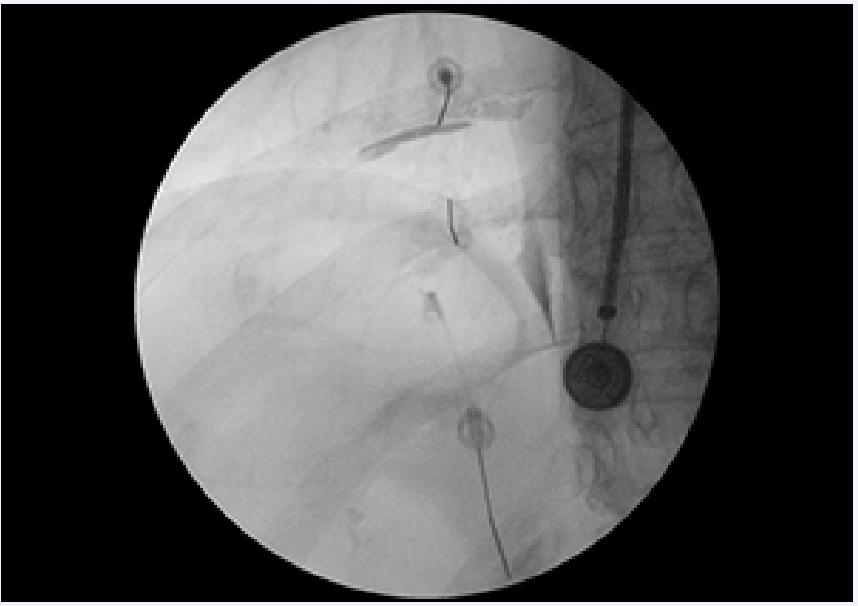

Intercostal blocks (ICNB) can be carried out above the Th10 level to localize the level of the pain with a target of > 50% reduction of pain during the local anesthetic blockade. Determining which nerve is causing the pain based on clinical examination is sometimes difficult because the innervations of intercostal nerve overlap [19] (Figure 1).

Left sided Intercostal nerve injection under fluoroscopy with  contrast.

Figure 1: Left sided Intercostal nerve injection under fluoroscopy with contrast.

Therefore, diagnostic blocks of intercostal nerves are usually performed at 3 levels. The injection can be done under fluoroscopy or with ultrasound guidance [20]. A study done in cadavers [21] confirmed that US confers higher accuracy and allows use of lower volumes of injectate compared with anatomic landmarks as a guide method for ICNBs. The intercostal neurovascular bundle runs in the lower part of the inner side of the rib and cannot be visualized with US, the use of US guidance is recommended since imaging of the needle tip and the pleura in real-time could potentially reduce pneumothorax formation during block.

Once ICNBs are completed, the patient needs to be observed at least 30 minutes for symptoms or signs of local anesthetics toxicity; development of hematoma, cough, and shortness of breath, low oxygen saturation, or wheezing that may indicate pneumothorax. Complications of the ICNBs are quite rare: local anaesthetics toxicity, pneumothorax, bleeding, infection, neuropathic pain, paravertebral spread, hypotension, spinal anesthesia [22].